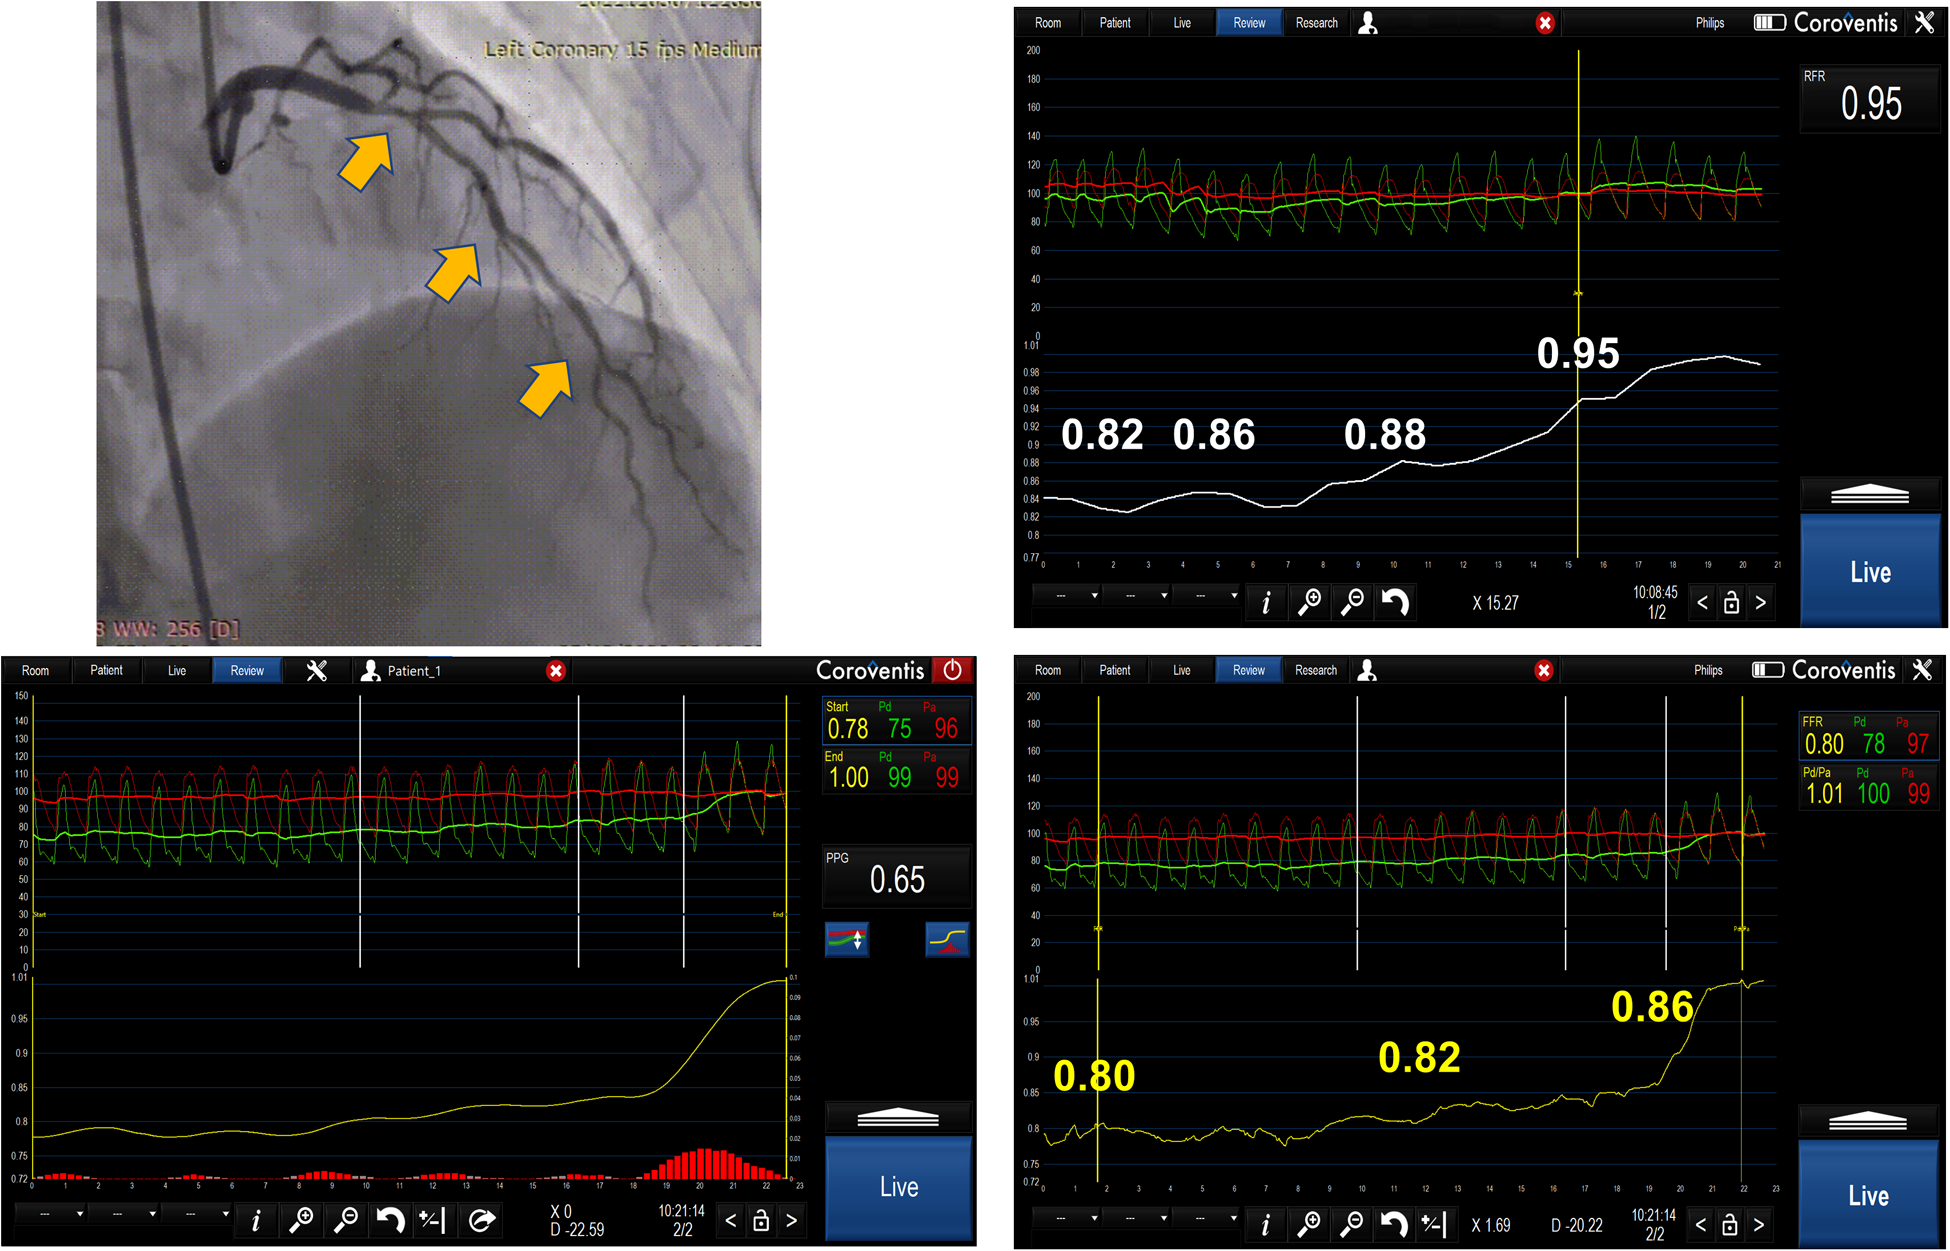

The concept of PPG was applied to patients with serial stenoses, and it identified three distinct functional FFR phenotypes based on FFR curve pullbacks: one indicating diffuse disease with no step-up during pullback with low PPG values, second with FFR pullback curves with one step up, and finally an FFR pullback curve with two steps up and highest PPG values, indicating distinct stenoses that can be best served by PCI (21), (Figure 5). The use of PPG in guiding serial stenosis evaluation and PCI has not been systematically compared to FFR and NHI pullback, so it cannot replace already accepted methods in the algorithm of serial stenosis evaluation and treatment. In our opinion, PPG can be a new step in the evaluation that could help us to better identify the patients with true separate lesions that can be best served by PCI compared to the patients that have the diffuse disease and in whom, despite significant FFR or NHI values, optimal medical therapy might be a good solution.

Figure 5

The image represents serial lesion assessment in a 39 year-old patient using resting full-cycle ratio (RFR) and FFR pullback with papaverine as the hyperemic agent. The obtained values were abnormal for RFR and normal for FFR. The possible reason for this could be that there was a diffuse atherosclerotic disease and pullback pressure gradient (PPG showing an intermediate value of 0.65) and the operator decided to defer revascularization due to a normal FFR value and diffuse disease in the left main and LAD.